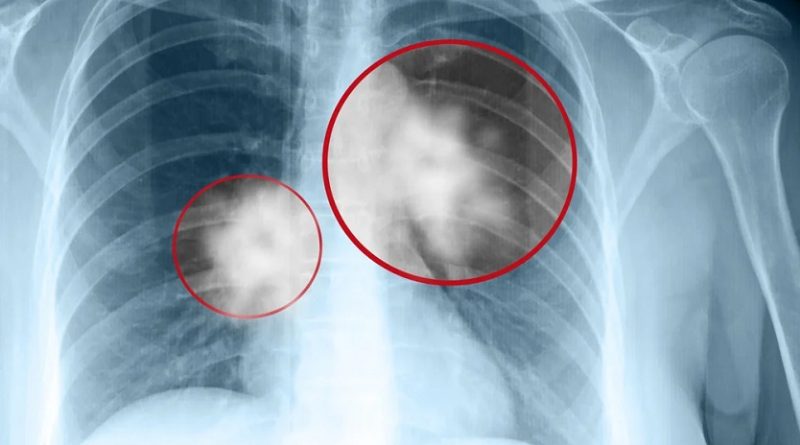

INCIDENȚA CANCERULUI PULMONAR ÎN JUDEȚ

Județul Hunedoara ocupă primul loc în zona de Vest a țării